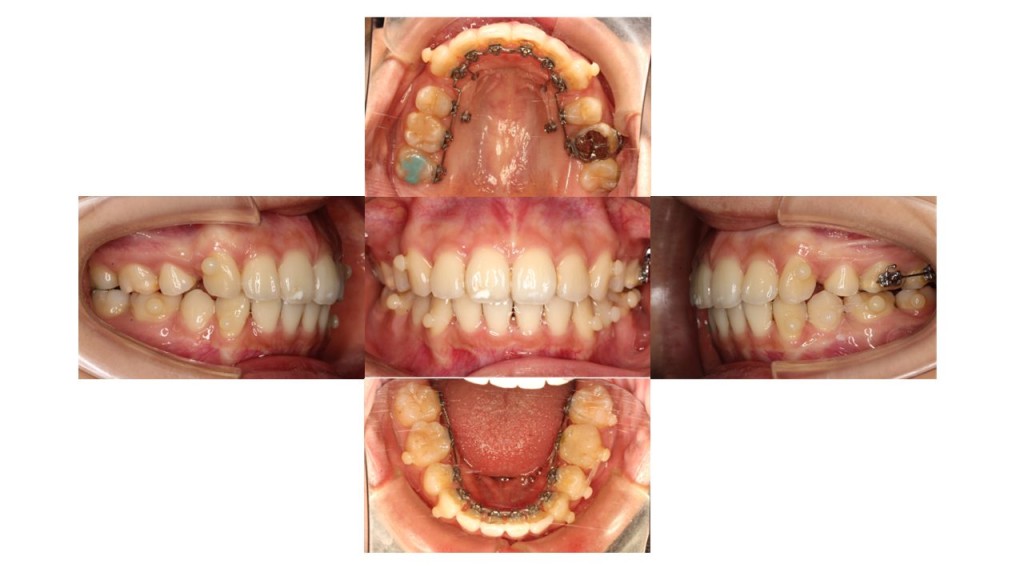

1年1ヵ月経過の口腔内の状態です。

上顎に歯科用アンカースクリューを埋入し、ゴムの力を使って前歯を引っ張りながら抜歯したスペースを閉じていきます。

患者様にも表側のゴムかけをご協力いただいております。(1日20時間目安)